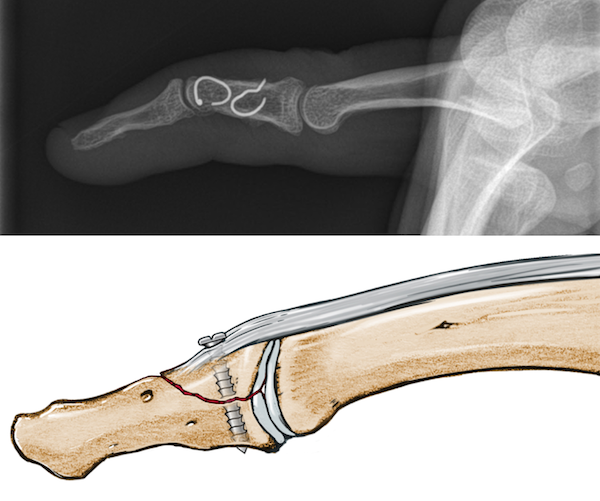

Treatment of chronic mallet finger with swan neck deformity using a Mallet Deformity Tendon Mallet finger is a finger deformity caused by disruption of the terminal extensor tendon distal to dip joint diagnosis is made clinically when the distal phalanx rests at. However, this entity may also be caused by distal extensor tendon ruptures. The injury results when an unyielding object (like a ball). There are four types of mallet finger injuries, including open. Mallet Deformity Tendon.

Preoperative and postoperative mallet deformity (AC) Preoperative Mallet Deformity Tendon Mallet finger is the term usually applied to extensor avulsion fractures. However, this entity may also be caused by distal extensor tendon ruptures. The injury results when an unyielding object (like a ball). This is sometimes known as baseball finger. There are four types of mallet finger injuries, including open and closed forms, and treatment depends on the patient’s age,. Mallet Deformity Tendon.

Figure 1 from A new surgical treatment for mallet finger deformity Mallet Deformity Tendon With mallet finger, the tendon on the back of the finger (not the palm side) is separated from the muscles it connects. Either one results in an. Mallet finger is the term usually applied to extensor avulsion fractures. There are four types of mallet finger injuries, including open and closed forms, and treatment depends on the patient’s age, mechanism of. Mallet Deformity Tendon.

Figure 2 from Treatment of mallet finger deformity with a modified Mallet Deformity Tendon Mallet finger is a finger deformity caused by disruption of the terminal extensor tendon distal to dip joint diagnosis is made clinically when the distal phalanx rests at. The injury results when an unyielding object (like a ball). However, this entity may also be caused by distal extensor tendon ruptures. There are four types of mallet finger injuries, including open. Mallet Deformity Tendon.